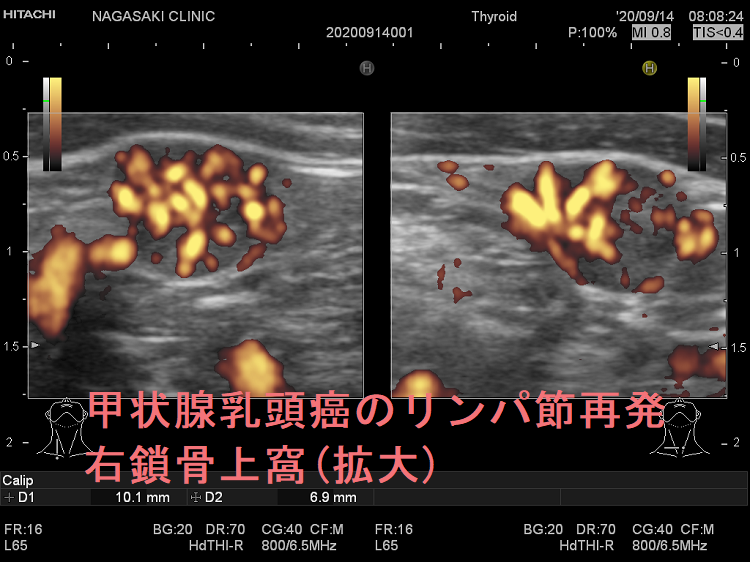

甲状腺乳頭癌鎖骨上窩リンパ節転移再発

甲状腺乳頭癌のリンパ節再発 右鎖骨上窩 超音波(エコー)画像

甲状腺乳頭癌のリンパ節再発 右鎖骨上窩 超音波(エコー)画像;いびつな形で、周囲との境界が一部不明瞭化して浸潤を疑われる。リンパ門は消失し、砂粒状石灰化を認める。

甲状腺乳頭癌のリンパ節再発 右鎖骨上窩 超音波(エコー)画像 ドプラーモード

甲状腺乳頭癌のリンパ節再発 右鎖骨上窩 ドプラーモード;内部に異常な走行の血管を認め、血流豊富。

甲状腺乳頭癌のリンパ節再発 右鎖骨上窩 超音波(エコー)画像(拡大)

甲状腺乳頭癌のリンパ節再発 右鎖骨上窩 超音波(エコー)画像(拡大);いびつな形で、周囲との境界が一部不明瞭化して浸潤を疑われる。リンパ門は消失し、砂粒状石灰化を認める。

甲状腺乳頭癌のリンパ節再発 右鎖骨上窩 超音波(エコー)画像 ドプラーモード(拡大)

甲状腺乳頭癌のリンパ節再発 右鎖骨上窩 ドプラーモード(拡大);内部に異常な走行の血管を認め、血流豊富。